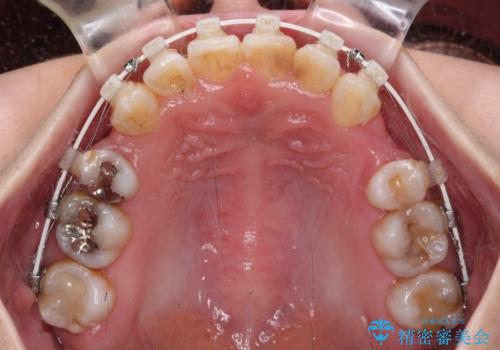

- 矯正装置

- 審美装置

- 上下の八重歯と前歯のデコボコを気にして来院された患者様です。

右上と左下の八重歯が特に著しく、上顎正中が右側にシフトしていました。

デコボコが強いため小臼歯4本を抜歯し、上顎正中を左側に移動させるために補助装置を使用して、ワイヤー装置にて矯正治療を行うこととしました。

八重歯のためずれていた上下の正中をほぼ一致する位置に整えることができました。

重なって汚れの溜まりやすかった部分も改善され、大変満足していただけました。